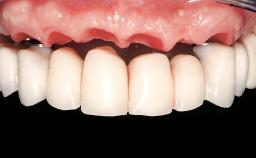

Immediate Loading of Six Implants in the Mandible and Six Implants in the Maxilla and Final Restoration with Full-Arch CAD/CAM Metal Framework FDPs Involving Digital Planning and Guided Surgery

Ali Tahmaseb, Renaat De Clerck, Daniel Wismeijer

Immediate loading of dental implants is increasingly popular with clinicians and patients. The idea of delivering a restoration directly after implant insertion,combined with a less invasive procedure (flapless protocol), has made treatment protocols involving dental implants more accessible to dentists and patients. However,immediate-loading concepts require sophisticated and exact planning. To facilitate this, conventional panoramic tomographs and periapical radiographs are often taken with the patient wearing a radiographic template simulating the preoperative prosthetic design. However, these radiographs do not provide all the necessary information. In addition, some protocols call for conventional surgical templates fabricated on the diagnostic cast. These will inform the bone drilling points and drill angles, but do not reference the underlying anatomical structures or provide exact 3-D guidance.